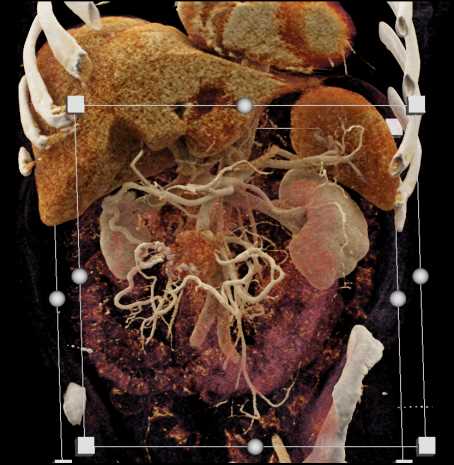

Carcinoid Tumor with Desmoplastic Reaction